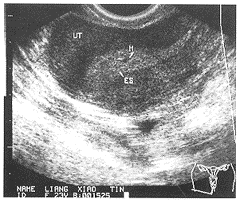

经阴道超声对宫内残留胎物的诊断价值